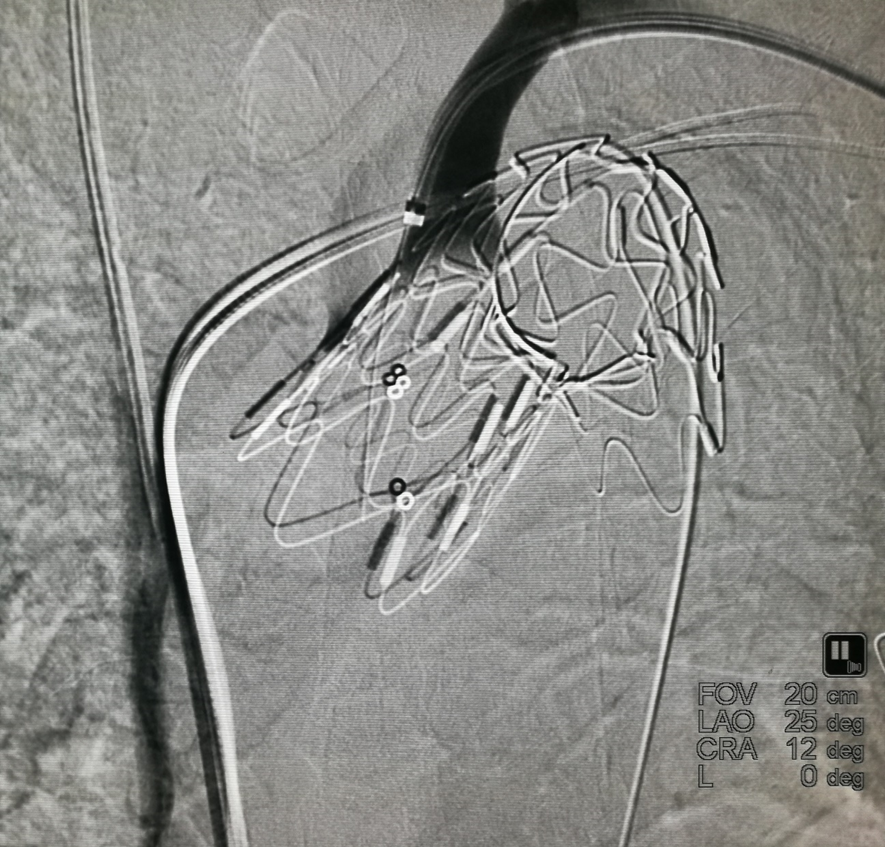

我们在两头35kg巴马公猪中完成动物实验:

成功实现弓上分支的快速、准确原位开窗;

破膜过程流畅,无分支或主动脉损伤;

取出标本可见圆形破口、支架贴合良好,证实技术可行性。

动物实验

巴马公猪35kg